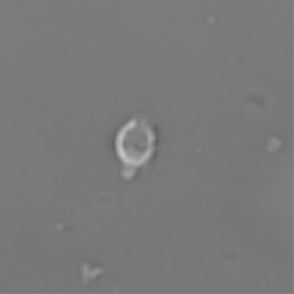

(a) Frame 1. Cell attachment phase

(b) Frame 2. Beginning of cell spreading

Figure 3: Original images of sequence is example of high dynamics of cell behavior affecting on contrast properties

The Fig.3 is representing couple of frames of sample image sequence with relatively high contrast between foreground and can be segmented with almost 95% accuracy with any method we used. Frame 1 of sample sequence presented at Fig.3(a) contain regions of hyper contrast pixels. In this case such condition does not affect on valid recognition since they are belong to object and present on margins of it and differs well from background. For Frame 2 there is absence of such pixels (Fig.3(b)) and this conditions also makes segmentation possible in relatively inflexible filtering conditions. The Frame 2 has relatively low contrast however it is seen that after filtration applied on image we achieve good difference of core and cell body compared to background as it presented at Fig.4 .